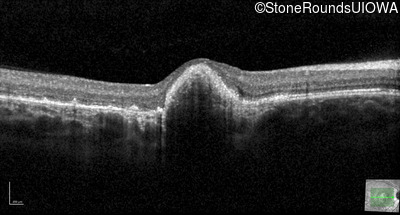

Optical Coherence Tomography - Right - 20/100 sc

Exemplar / OCT Stack